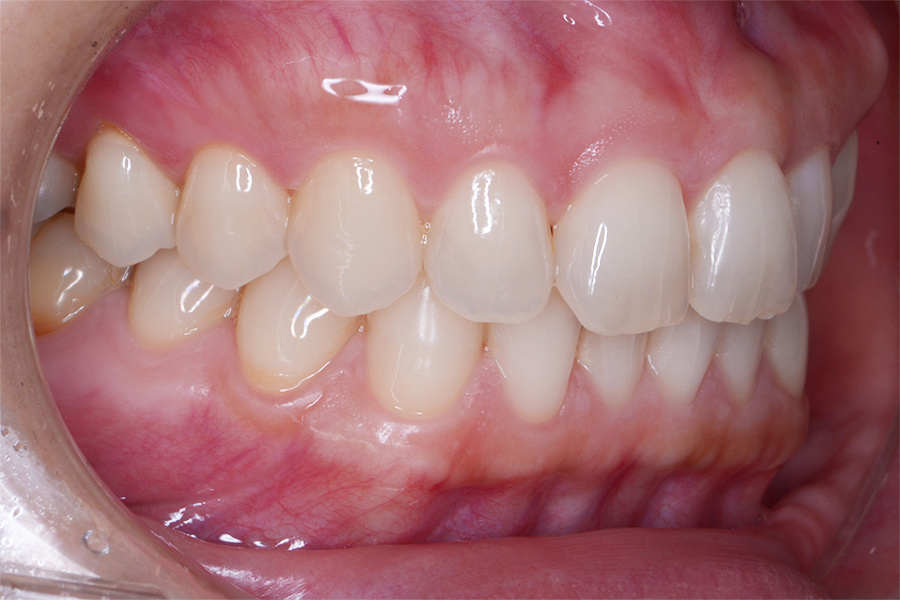

• 治療前

主訴 真ん中二本の捻じれた歯を治したい

期間 治療期間8か月

治療内容 上顎リンガル矯正(裏側矯正)